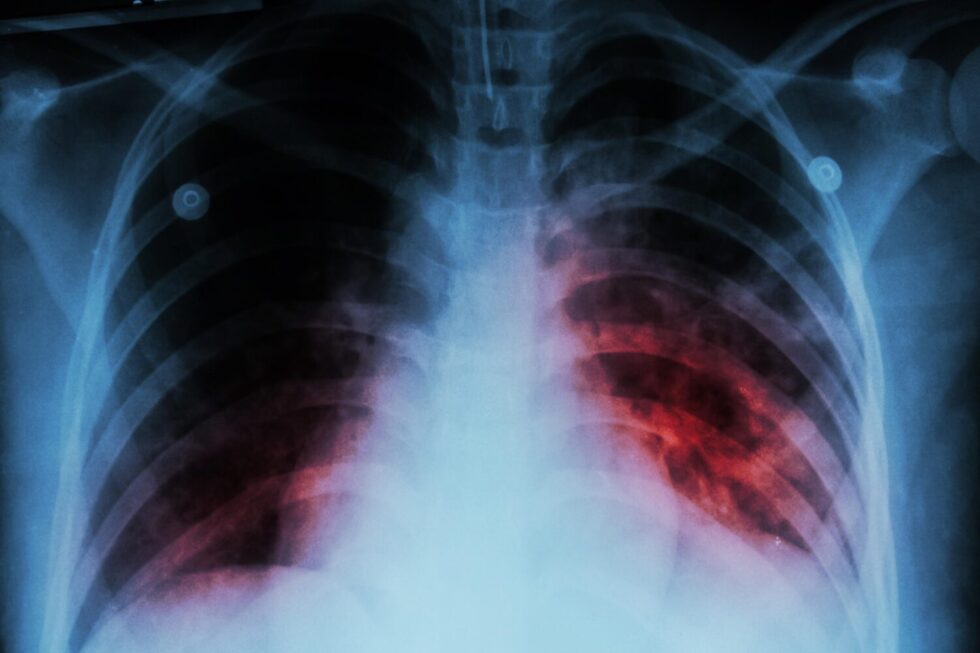

El diagnóstico se confirma a través de pruebas moleculares, cultivo de esputo y radiografías de tórax, herramientas esenciales para detectar la enfermedad en sus primeras etapas y evitar complicaciones graves.